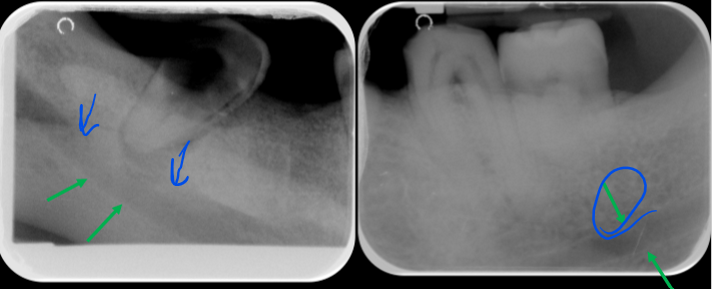

Why will an object appear wider on a radiograph?

Object is lingual in the focal trough